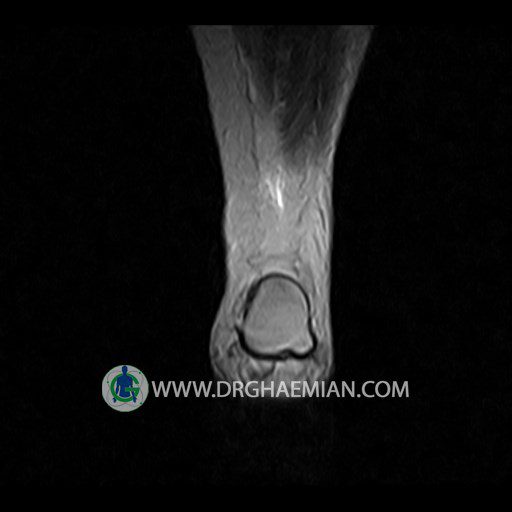

پزشکان اغلب از تصویربرداری ام آر آی برای تشخیص و درمان عارضه های پزشکی که فقط با استفاده از اشعه ایکس یا میدان مغناطیسی و امواج رادیویی قابل مشاهده است، استفاده می کنند. دستگاه ام آر آی تصاویر دقیق از ساختار های داخلی بدن ایجاد می کند. در این کیس تورم مچ پا بیمار مشاهده می شود.

Technique: Sagittal T1, T2 , Axial GE , coronal & sagital fatsat .

– Mild soft tissue swelling around the knee

is seen